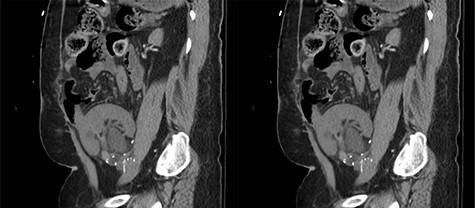

Our patient is a 35-year-old female with a history of Type 1 diabetes and hypertension who underwent SPK transplantation in 2015. The pancreas transplant was performed with systemic venous drainage and enteric exocrine drainage. Kidney transplantation was performed intraperitoneally in the left lower quadrant, with standard anastomoses performed between left external iliac vessels and renal artery/vein [1]. She presented to the emergency room 5 years after her transplantation with 24 h of severe Lt lower abdominal pain, nausea and vomiting with tachycardia and leukocytosis up to 22.6. The patient was diagnosed with sepsis secondary to UTI. Upon evaluation, she was anuric, and her creatinine was 5.45 mg/dl from 2.15. Computed tomography (CT) abdomen pelvis without contrast showed hydronephrosis of the donor kidney (Fig. 1). Doppler ultrasound was performed and showed no flow to the donor kidney (Fig. 2). She was urgently taken to the operating room for exploration. Intraoperatively, we found that the renal artery and vein of the transplanted kidney was strangulated by the left fallopian tube and respective ovary (Fig. 3). The transplanted kidney was noted to be gangrenous and ischemic (Fig. 4). In addition, intraoperative Doppler confirmed no arterial blood flow, and the decision was made to perform a transplant nephrectomy. The remainder of her hospital course was unremarkable. The patient was subsequently re-listed for a kidney transplant.

Coronal view of the CT abdomen pelvis without contrast showing hydronephrosis of the donor’s kidney.